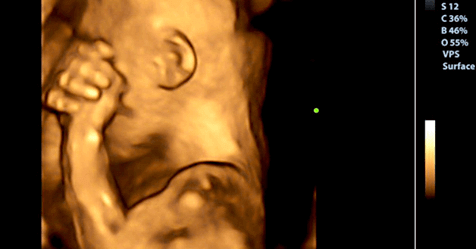

Esta pesquisa descobriu que quando um bebê está no útero de sua mãe, é um participante ativo no seu próprio desenvolvimento, especialmente porque ele está a recolher informação para a vida extra uterina durante esse período. Um dos achados mais impressionantes do trabalho científico de que também participaram Elysia P. Davis e Laura M. Glynn é que o bebê pode sentir o estado psicológico da mãe.

À medida que o bebê cresce, recebe constantemente mensagens de sua mãe e estas não são apenas circunscritas para ouvir seu batimento cardíaco ou ouvir a música que sua mãe o coloca perto de sua barriga: vai além. Nesse estágio, o bebê recebe sinais químicos através da placenta, que incluem o estado mental de sua mãe. Os hormônios que as mães produzem quando experimentam emoções passam pela placenta.